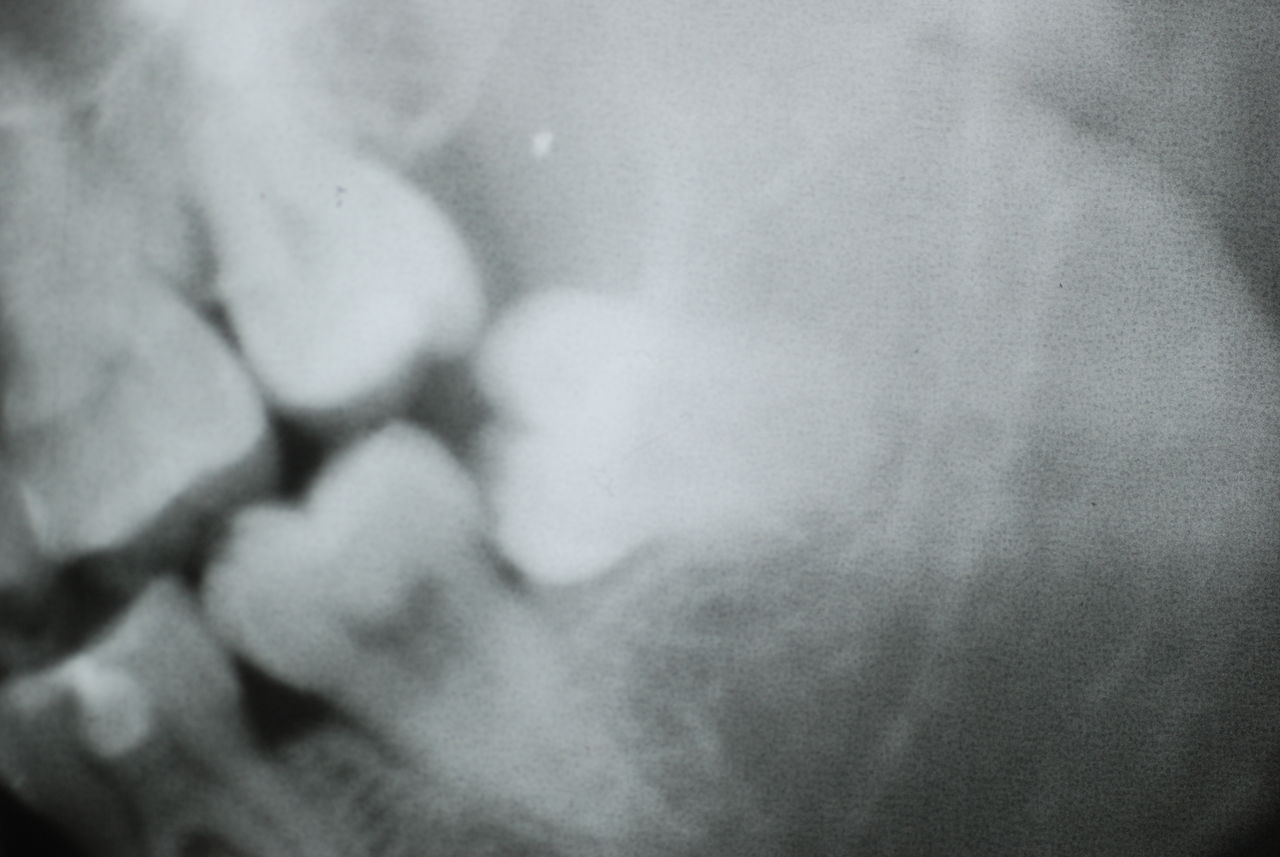

レントゲンでは小さいですが、こう言う虫歯が一番怖いのです。

隣の14歳大臼歯がひどい虫歯になり治療不可能になりつつある状態のレントゲン